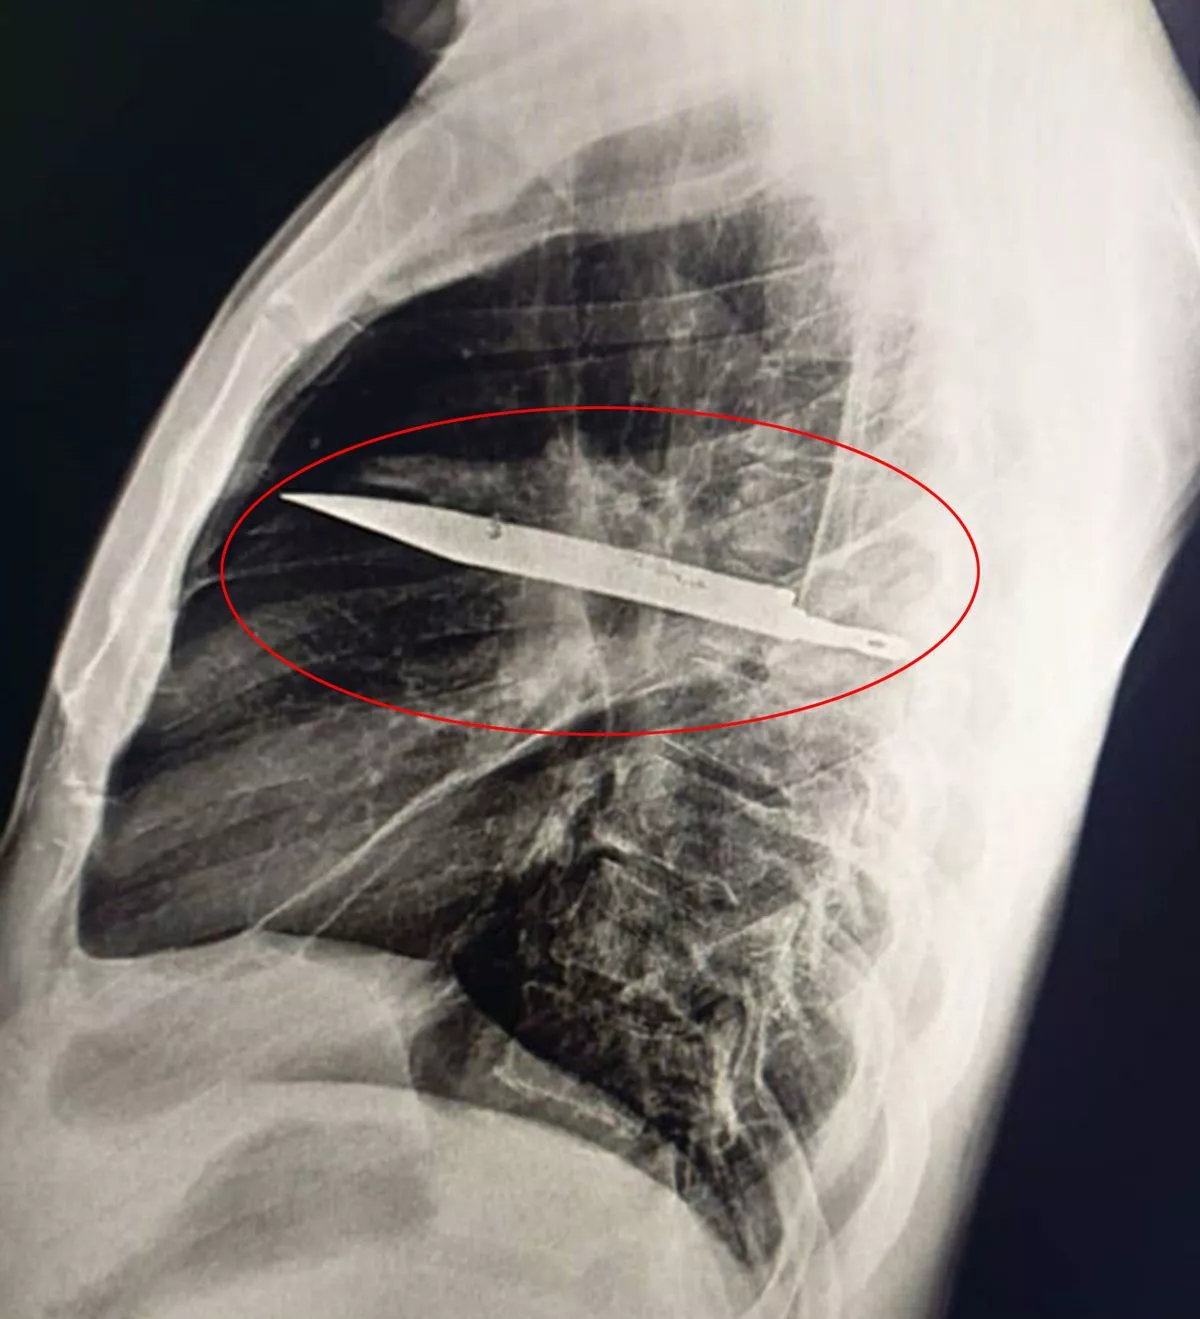

Une radiographie thoracique a été réalisée après sa plainte et elle a révélé la cause de son mal actuel : une grande lame de couteau logée au milieu du thorax.

Les médecins ont constaté que le couteau avait pénétré l’omoplate droite et avait réussi à éviter les organes vitaux.